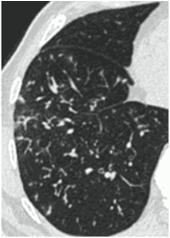

КТ имеет высокую чувствительность в выявлении изменений в легких, характерных для COVID-19. Применение КТ целесообразно для первичной оценки состояния ОГК у пациентов с тяжелыми прогрессирующими формами заболевания, а также для дифференциальной диагностики выявленных изменений и оценки динамики процесса. КТ позволяет выявить характерные изменения в легких у пациентов с COVID-19 еще до появления положительных лабораторных тестов на инфекцию с помощью методов амплификации нуклеиновых кислот. В то же время, КТ выявляет изменения легких у значительного числа пациентов с бессимптомной и легкой формами заболевания, которым не требуется госпитализация. Результаты КТ в этих случаях не влияют на тактику лечения и прогноз заболевания при наличии лабораторного подтверждения COVID-19. Поэтому массовое применение КТ для скрининга асимптомных и легких форм болезни не рекомендуется.

3. Применение лучевых методов у пациентов с симптомами ОРВИ легкой степени тяжести и стабильном состоянии пациента, возможно только по конкретным клиническим показаниям, в том числе, при наличии факторов риска, при условии достаточных технических и организационных возможностей. Методом выбора в этом случае является КТ легких по стандартному протоколу без внутривенного контрастирования или РГ при ограниченной доступности КТ. Использование УЗИ в этих случаях нецелесообразно.